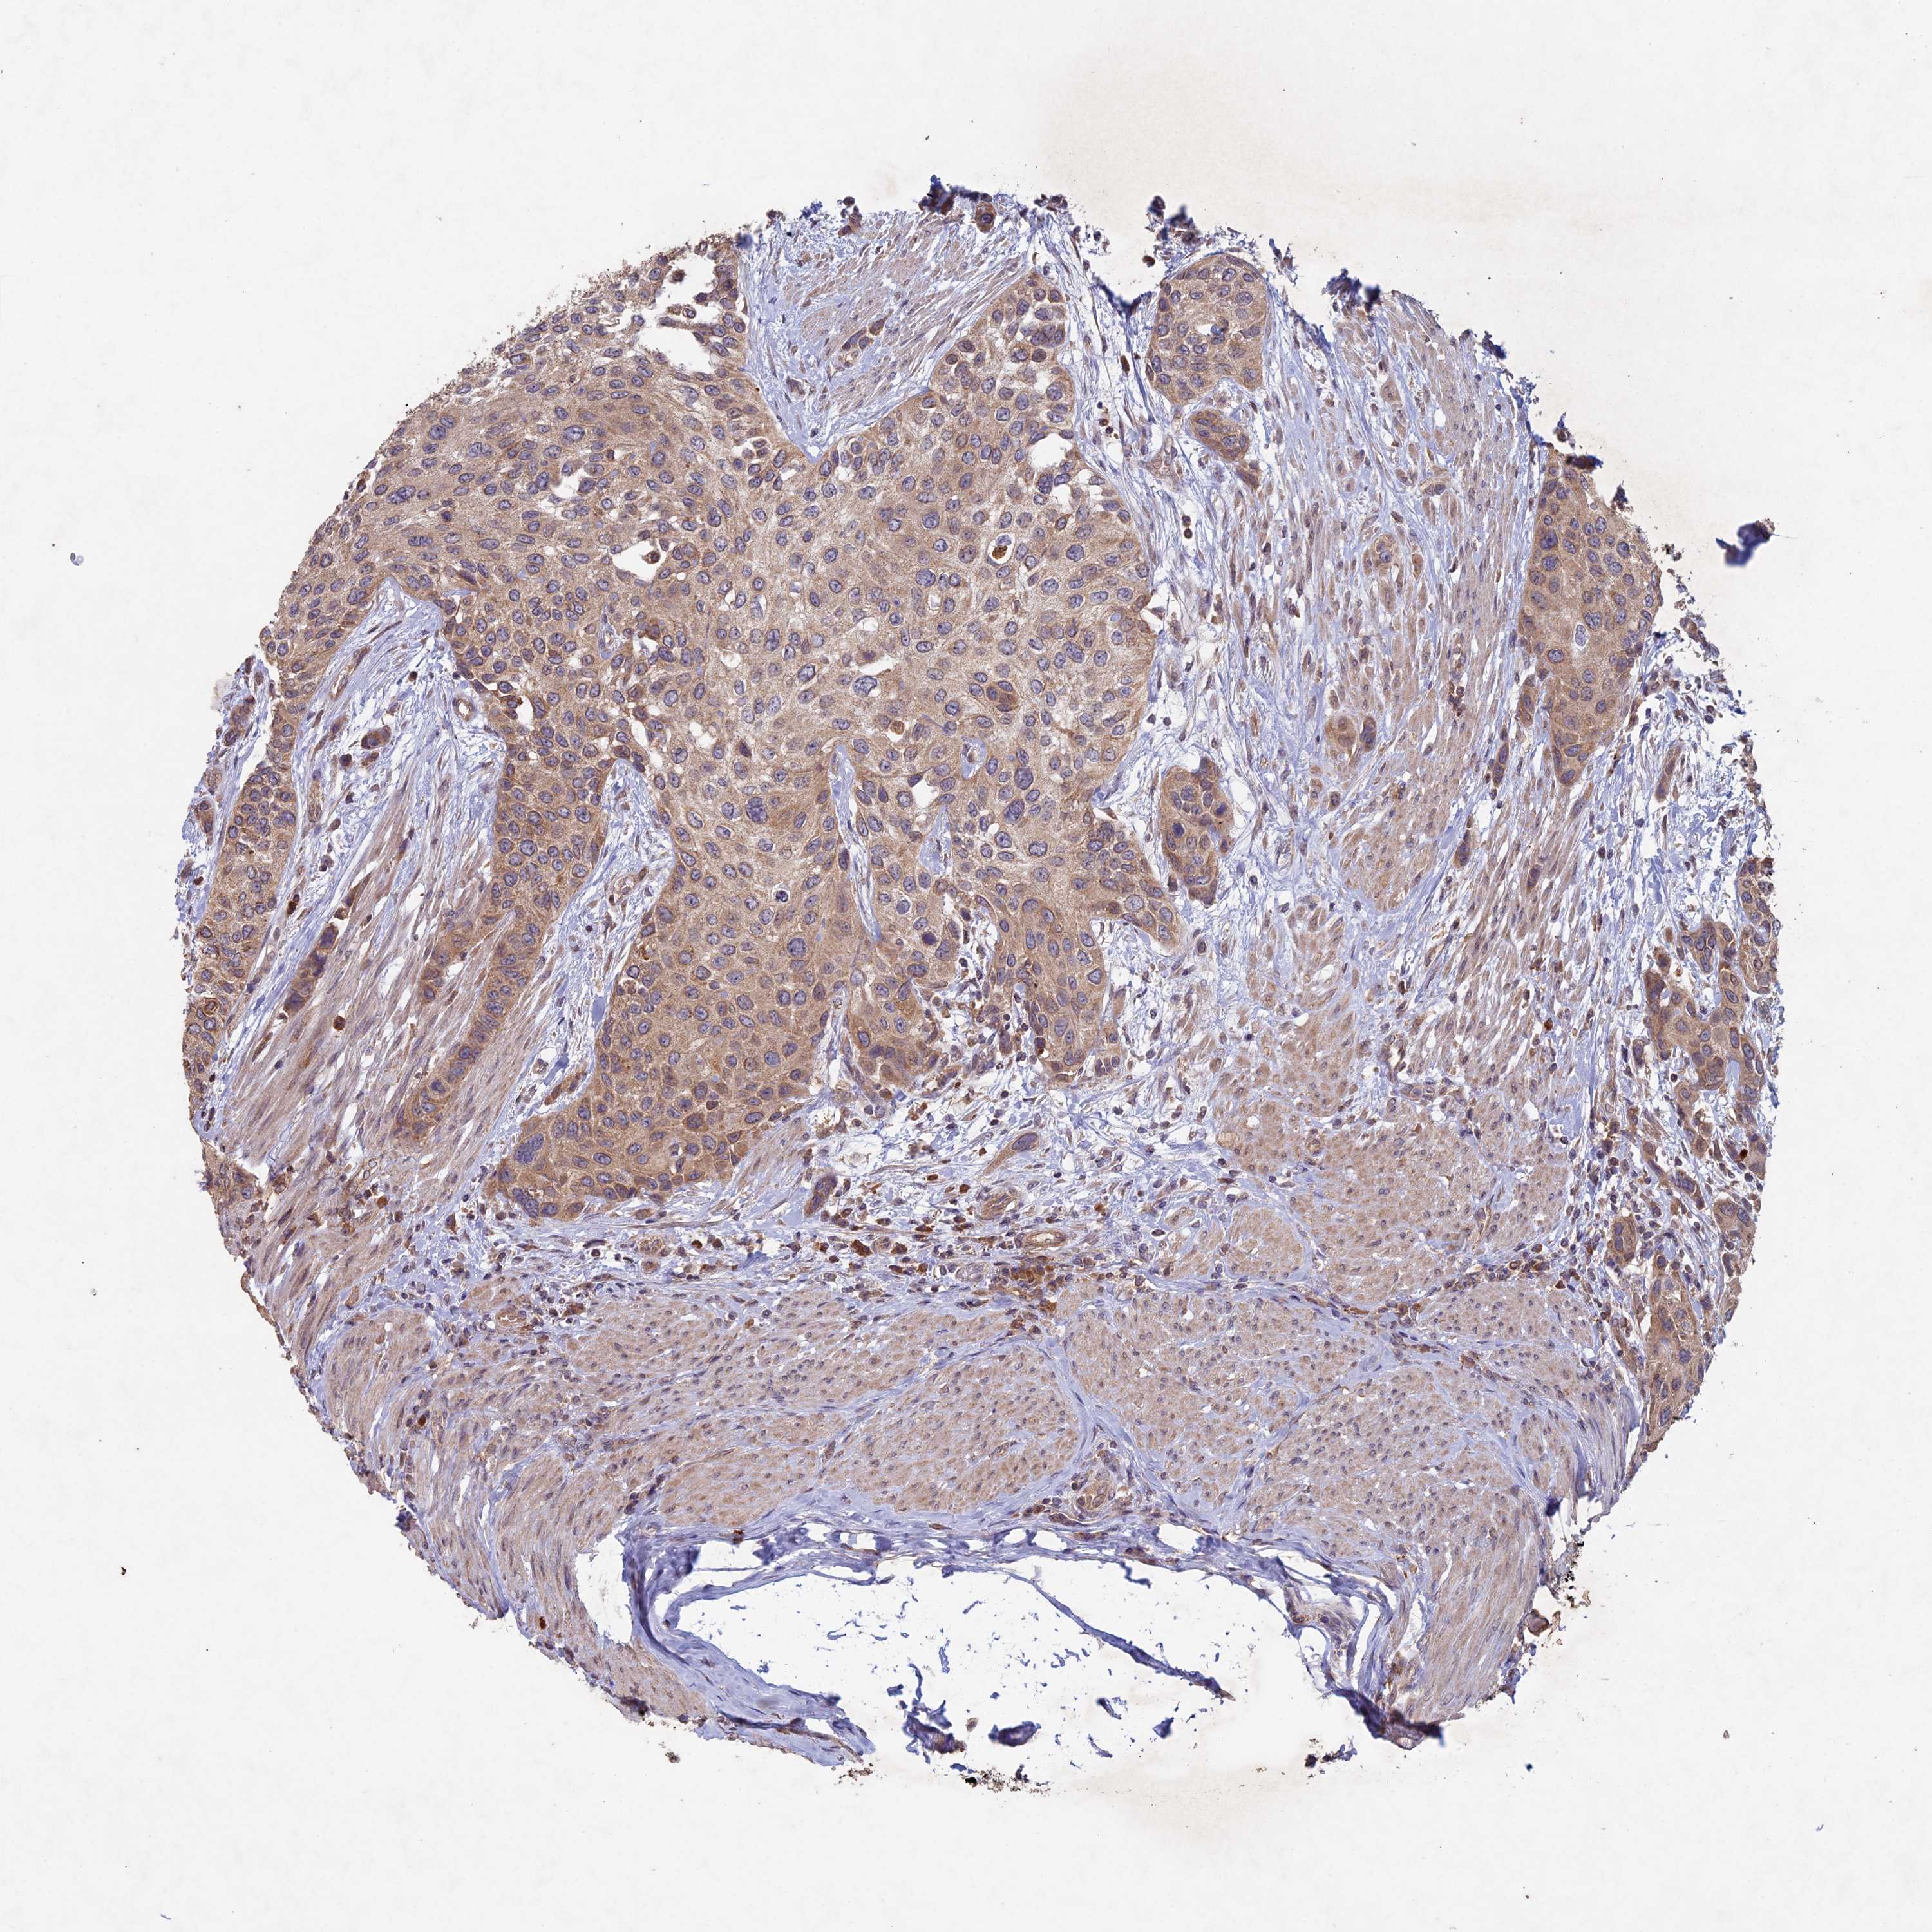

UROTHELIAL CANCER - Protein expressioni

A mouse-over function shows sample information and annotation data. Click on an image to view it in a full screen mode. Samples can be filtered based on level of antibody staining by selecting one or several of the following categories: high, medium, low and not detected. The assay and annotation is described here.

Note that samples used for immunohistochemistry by the Human Protein Atlas do not correspond to samples in the TCGA dataset.

Antibody stainingi

Antibody staining in the annotated cell types in the current human tissue is reported as not detected, low, medium, or high, based on conventional immunohistochemistry profiling in selected tissues. This score is based on the combination of the staining intensity and fraction of stained cells.

Each image is clickable and will lead to virtual microscopy that enables deeper exploration of all samples and also displays staining intensity scores, fraction scores and subcellular localization as well as patient and tissue information for each sample.

Antibody HPA039683

Antibody HPA040776

Urothelial carcinoma, High grade

Urothelial carcinoma, Low grade